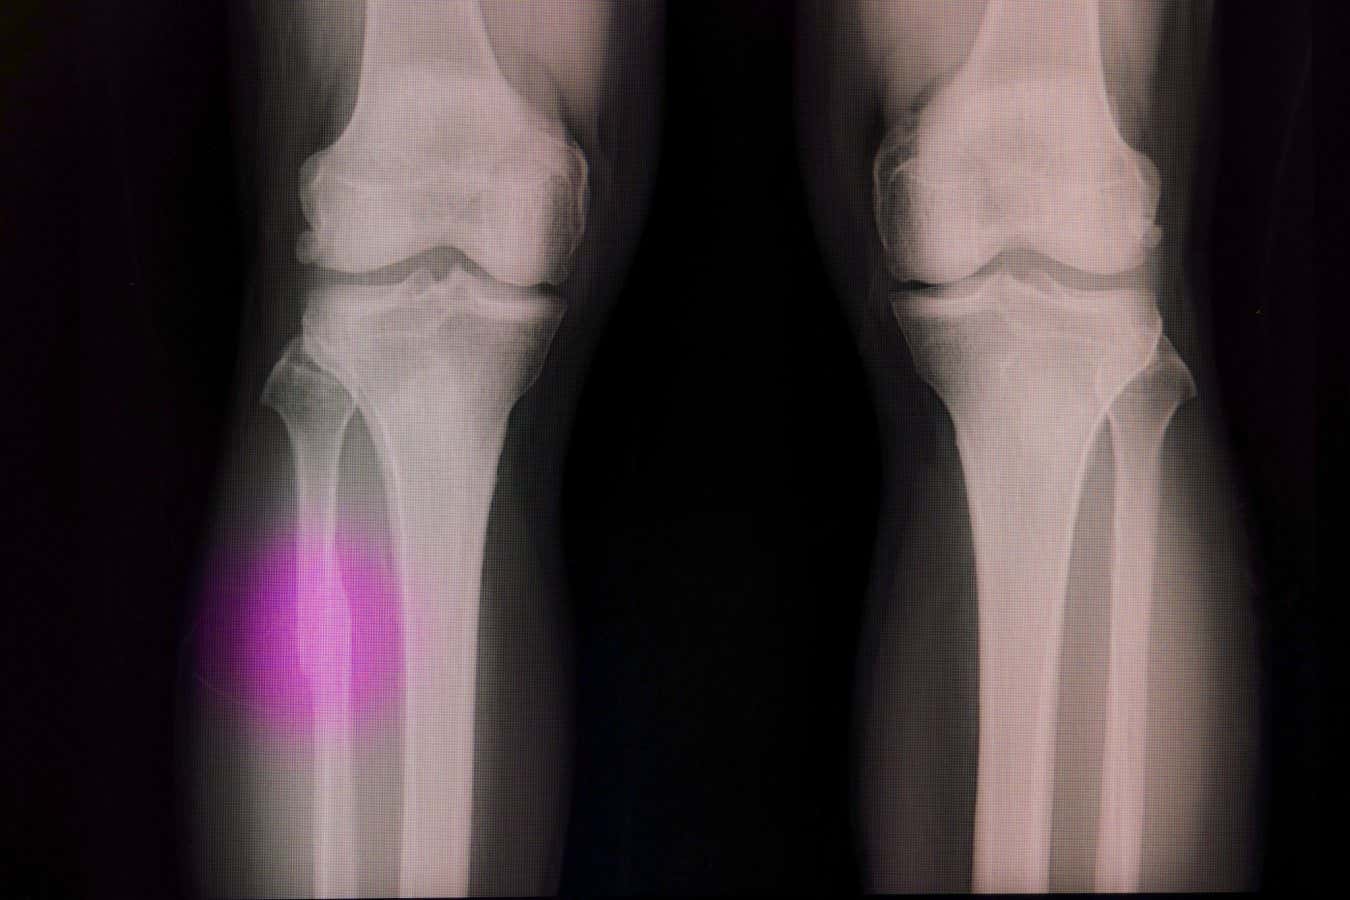

Broken bones often need a material to fill the void

Sopone Nawoot/Alamy

Bones can repair themselves after small injuries, but if there is a void , because of serious trauma or tumour removal, for example , then that space needs to be filled with either a graft or an artificial plug made of a material that encourages bone cells to spread.